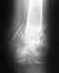

Re: Кость так и не срастается

Вариантов действий несколько, 1)можно просто подождать (неизвестно сколько, и есть немалые шансы так и не дождаться),

2)можно наложить упрощенный аппарат на локтевую кость, чтобы сдавить поверх стержня,

3)стержень заменить на больший по диаметру, с возможностью компрессии,

4)заменить стержень на пластину с костной пластикой.

Оптимальны варианты 2 или 3. Наверно, есть смысл приехать к нам на очную консультацию.